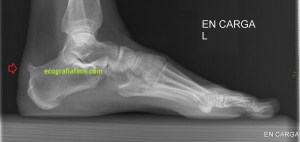

Corrobora si el paciente tiene estudios radiológicos simples que estén en concordancia con la imagen 10, por ejemplo, la imagen 12.

La flecha amarilla indica la que en la parte posterior del calcáneo existe un calcio tosco en esta rx lateral del pie en carga, pero es en la inserción, cuidado con esto, cuando se produce el Haglund, no es en la inserción, es antes, y se debe a la exostosis mencionada con anterioridad, mira, compara imagen 12 e imagen 13. La flecha roja es indicativa de Síndrome de Haglund.